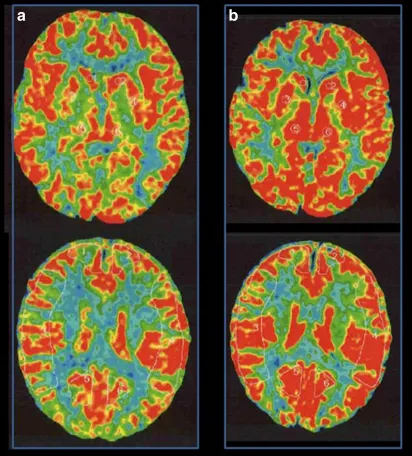

MRI没有发现脑卒中病变,但基底节有多个血流空洞。MRA显示右颅内颈内动脉末端狭窄,左颈内动脉造影显示颈内动脉无狭窄,右大脑前动脉由左大脑前动脉经前连合动脉供血。右颈内动脉造影显示颈内动脉末端狭窄,大脑前动脉缺失,大脑中动脉较左动脉扩张,烟雾血管在颈内动脉顶部形成(图1)。氙-CT灌注成像技术Xe-CT静息时及负荷时对比,显示右侧大脑中动脉区脑血管反应为14.8%,与左侧相比,右侧大脑中动脉区域的血供摄取没有明显减少(图2)。

图2:术前Xe-CT显示静息状态无偏侧(a),注射丹木斯(Diamox)后右侧MCA区域脑血管反应性为14.8%(b)